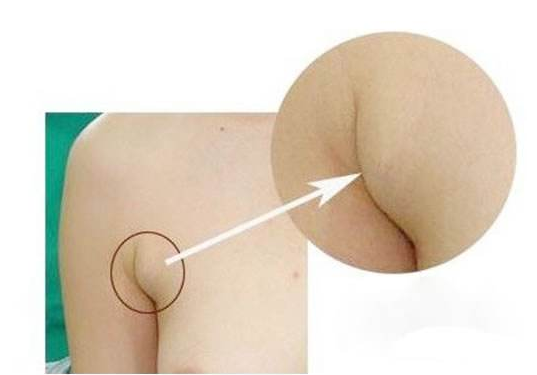

慢性淋巴結炎圖片

慢性淋巴結炎 (45)

慢性淋巴結炎 (46)

慢性淋巴結炎 (47)

慢性淋巴結炎 (48)

慢性淋巴結炎 (49)